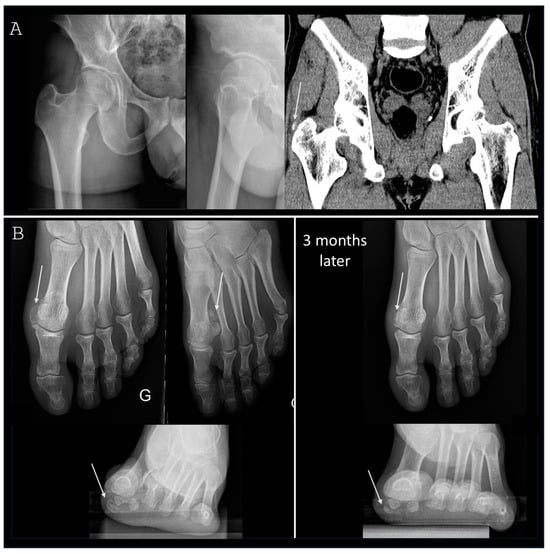

3.2. Lower Limb Involvement

- Park, S.M.; Baek, J.H.; Ko, Y.B.; Lee, H.J.; Park, K.J.; Ha, Y.C. Management of acute calcific tendinitis around the hip joint. Am. J. Sports Med. 2014, 42, 2659–2665. [Google Scholar] [CrossRef]